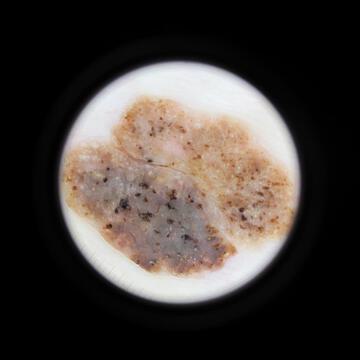

Case: 34